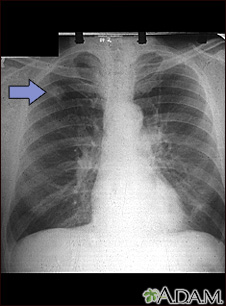

This chest x-ray shows adenocarcinoma of the lung. There is a rounded light spot in the right upper lung (left side of the picture) at the level of the second rib. The light spot has irregular and poorly defined borders and is not uniform in density. Diseases that may cause this type of x-ray result would be tuberculous or fungal granuloma, and malignant or benign tumors.